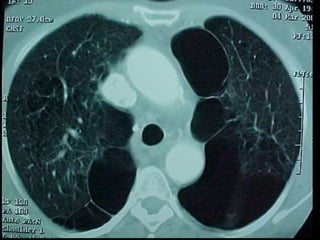

• Diagnóstico – Anamnese –Exame físico – Radiografia de tórax • Inspiração profunda (A) • Expiração profunda – TC de tórax